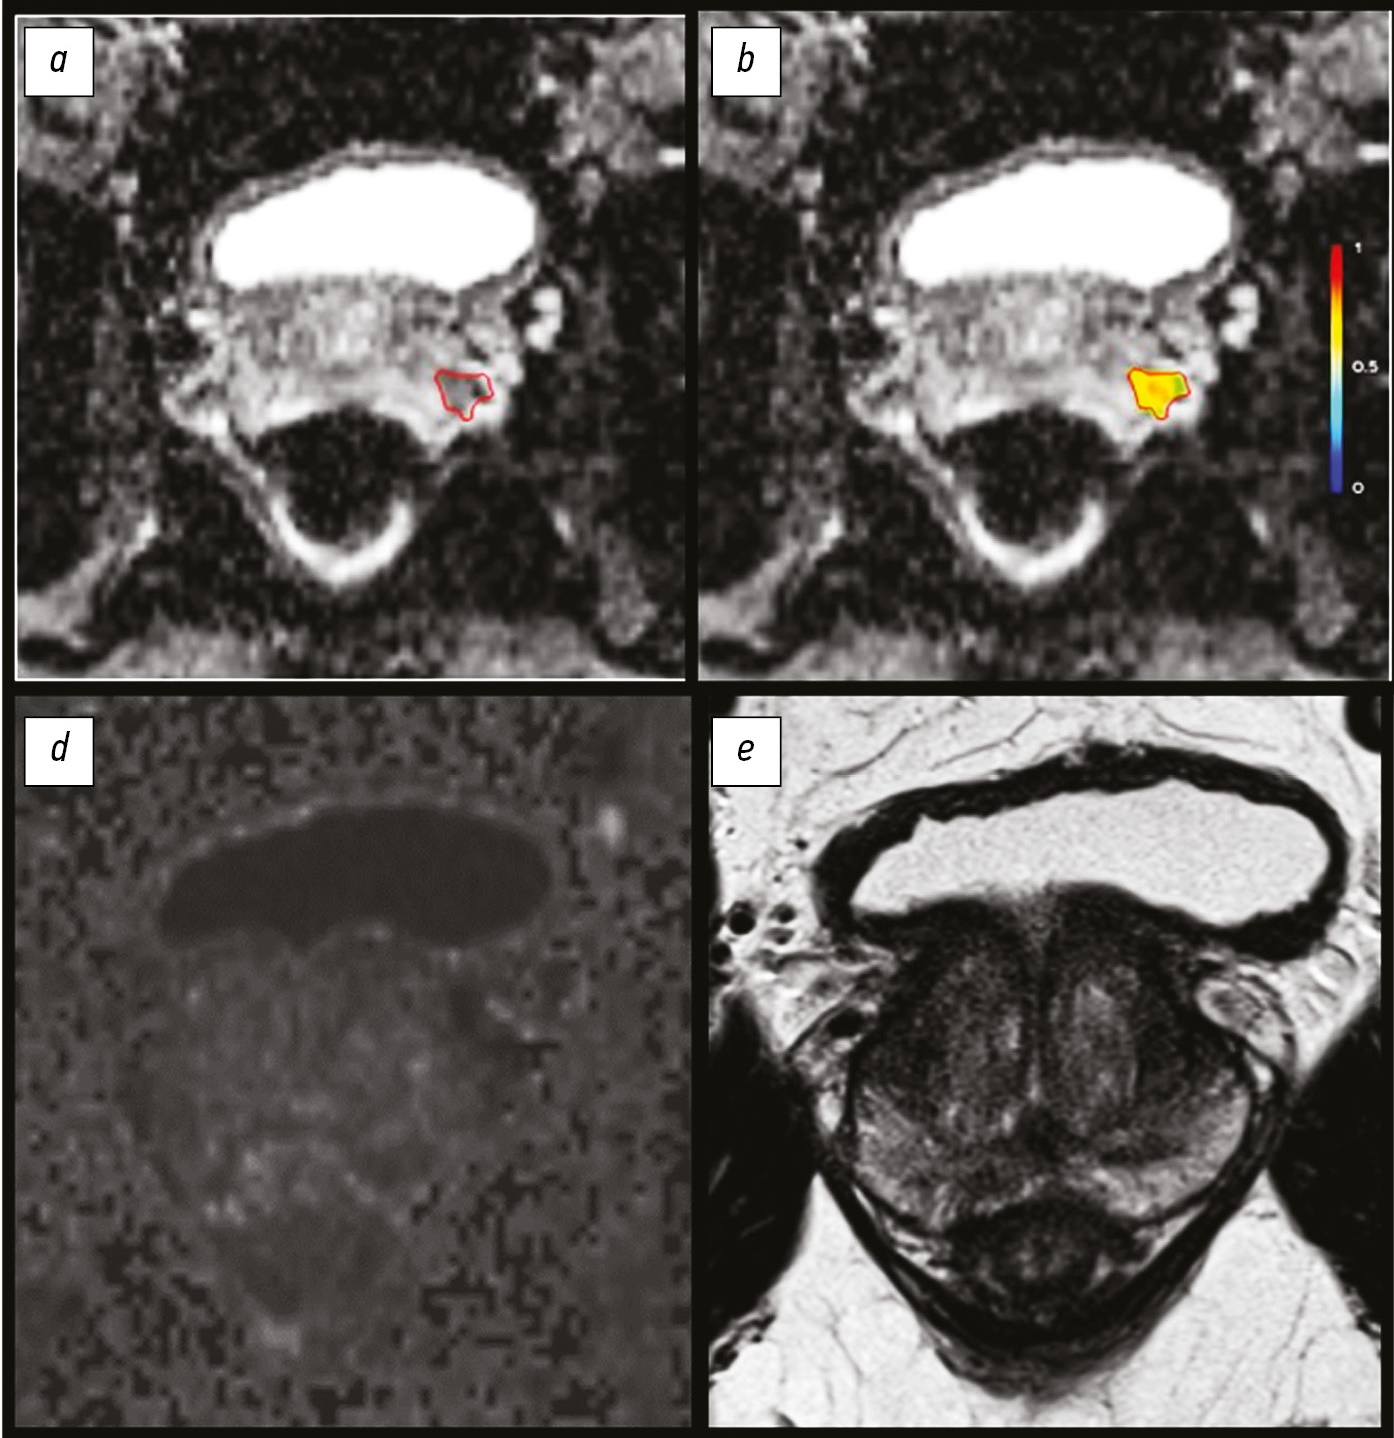

The increasing role of functional visualization modalities for navigation of external beam radiation therapy and brachytherapy in prostate cancer

Brachytherapy is successfully used in the treatment of malignant neoplasms in males and females and rare cases in children, as an independent method (with localized prostate cancer) or adjuvant with remote focal radiation therapy (with cancer of the cervix, anal canal, head and neck, breast, etc.).

The expansion of diagnostic capabilities (the advent of computer and magnetic resonance imaging) due to three-dimensional imaging has given brachytherapy an important technological advantage over other methods. Many options are available for combining brachytherapy with remote radiation or systemic antitumor therapy in the first line, as well as in a single mode for localized tumor recurrence in a previously irradiated area.

Intrastates (hollow tubes) for intra-tissue high-dose brachytherapy are administered during surgery and encapsulated (closed) radioactive micro-sources for low-dose brachytherapy are directly administered (percutaneously).

A distinctive feature of brachytherapy is a sharp drop in the dose outside the tumor focus, which minimizes the risk of irradiation of surrounding organs and tissues.

The main advantage of brachytherapy in comparison with remote radiotherapy is a higher radiation dose gradient at the tumor border (from all sides). Moreover, clarifying the boundaries of uncertainty when irradiating the target is unnecessary. When the tumor changes during treatment, the sources fixed in the tumor synchronously change their position.

In addition to the advantages in efficiency and safety, the total financial costs of brachytherapy are significantly lower than other radiotherapy options.

488-497